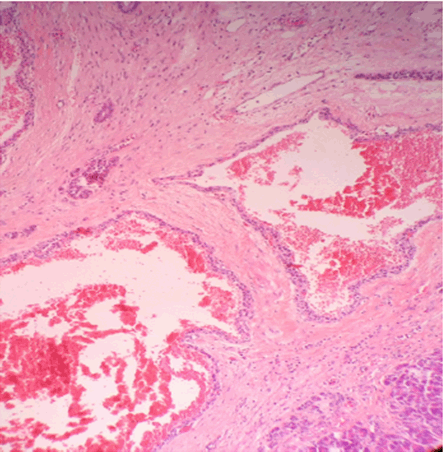

Clinical examination on admission revealed healthy looking women, comfortable, abdomen soft and no abdominal masses palpable. Blood tests including lipase, CEA and CA 19-9 were normal. Computed tomography scan and magnetic resonance imaging (MRI) scan showed a 19-mm cystic multi loculated lesion in the tail of the pancreas which was initially thought to be a serious cystadenoma. We decided to follow-up the lesions with MRI scan in three months’ time because of atypic characteristics of the lesion. Magnetic resonance imaging (MRI) at three month showed 24 mm cystic loculated lesion (increasing in size comparing to the last CT scan), well demarcated with a thick and contrast enhanced septa (Figure 1). No infiltration to the surrounding structure and no communication with the main pancreatic duct were described. Endoscopic ultrasound showed a 25-mm cystic lesion with same characteristics as on MRI scan and particularly did not find intramural nodule (Figure 2). For technical reason the puncture biopsy was not possible.

Figure 2: Endoscopic ultrasound showing lobulated cystic lesion in the tail of the pancreas with no Doppler signal.

There are several radiological modalities to diagnose pancreatic hemangioma. Ultrasound is helpful to diagnose the pancreatic hemangioma especially large size lesions (> 5 cm) as reported in nine cases. In the ultrasound they look like cystic lesion, hyper echogenic comparing to the rest of the pancreas with no Doppler signal comparing to malignant lesion which is well vascularized. In the endoscopic ultrasound they appear as cystic mass with thick septations with no Doppler signal. Most of the reported cases share the same ultrasonographic features [1].